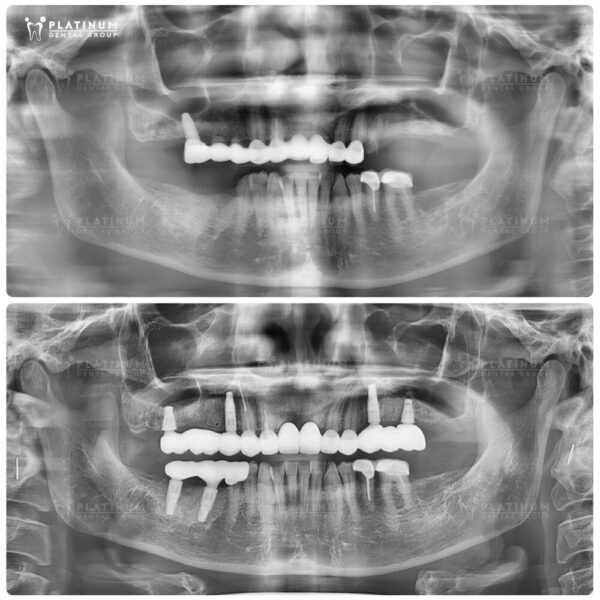

Cô Tuyết Hoa (65 tuổi), bị mất răng lâu năm khiến cho vùng xương và nướu đã bị tiêu biến, ảnh hưởng nghiêm trọng đến thẩm mỹ, chức năng ăn nhai và cả sự tự tin khi giao tiếp.

Trước khi đến Platinum Dental, cô Tuyết Hoa cso tình trạng cầu sứ nối răng thật với implant sai chỉ định, răng sứ mẻ liên tục do thiếu nâng đỡ khớp cắn phía sau. Tụt nướu, tiêu xương, nướu giả gây nhét thức ăn, hôi miệng, kém thẩm mỹ. Điều này làm cô thiếu tự tin trong giao tiếp. Để phục hồi cho cô, bác sĩ Dương Minh Tùng và team Platinum Dental đã thực hiện:

- Trồng implant vùng răng sau, tái lập khớp cắn, phục hồi sức nhai.

- Áp dụng kỹ thuật Ovate Pontic, loại bỏ nướu giả, tái tạo nướu tự nhiên với xâm lấn tối thiểu.

- Phục hình sứ thẩm mỹ, mang lại nụ cười hài hòa, tự tin.